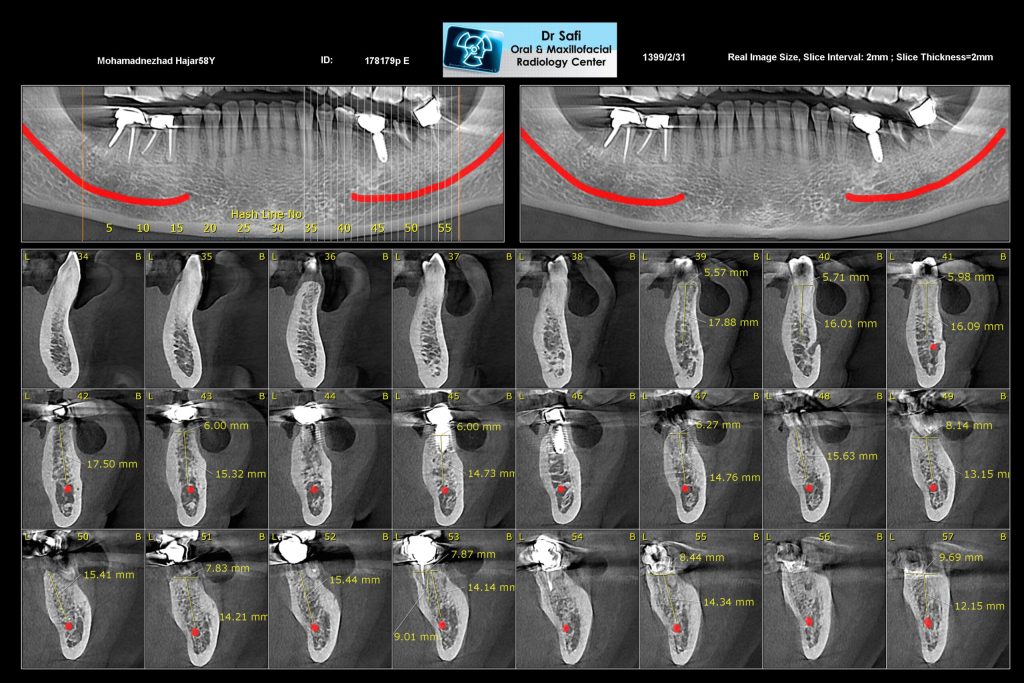

5. تصویربرداری سهبعدی (CBCT)

- تعریف: تکنیکهای تصویربرداری سهبعدی، مانند Cone Beam CT، تصاویری با کیفیت بالا و جزئیات دقیق از ساختارهای داخلی دهان ارائه میدهند.

- مزایا:

- ارائه نمای دقیق از موقعیت استخوانها، عروق خونی و عصبها

- ارزیابی فضای لازم برای قرارگیری ایمپلنت و کاهش عوارض جانبی

- کاربرد: این تصاویر به دندانپزشکان این امکان را میدهند که پیشبینی دقیقی از روند جراحی و نیاز به اقدامات اضافی داشته باشند.

درک فناوری CBCT

سیبیسیتی (CBCT)، که مخفف Cone Beam Computed Tomography است، نمایانگر یک پیشرفت قابل توجه در تکنولوژی تصویربرداری دندانپزشکی است. این تکنولوژی به تصاویر سهبعدی از ساختارهای دندانی و چهره بیمار با حداقل تابش نسبت به سیتی اسکنهای سنتی دست مییابد. این روش نقش حیاتی در افزایش دقت و ایمنی درمانهای دندانی، بهویژه ایمپلنتهای دندانی ایفا میکند.

1. ارزیابی جامع آناتومی

- ساختار و کیفیت استخوان: CBCT تصویری جامع از استخوان فک شامل ارتفاع، عرض و تراکم استخوان ارائه میدهد. این اطلاعات برای تعیین اینکه آیا استخوان میتواند بدون نیاز به پروسیجرهای اضافی ایمپلنت را به خوبی پشتیبانی کند، بسیار مهم است.

- نقاط آناتومیکی مهم: این تکنولوژی ساختارهای آناتومیکی حیاتی مانند اعصاب، رگهای خونی و حفرههای سینوسی را شناسایی میکند. در فک پایین، میتوان عصب مندیبل را مشاهده کرد که به جلوگیری از آسیب عصبی کمک میکند. در فک بالا، نزدیکی به سینوسها ارزیابی میشود تا از سوراخشدن سینوس جلوگیری شود.

2. دقت در قراردهی ایمپلنت

- برنامهریزی درمان شخصیسازیشده: اطلاعات دقیق بهدستآمده امکان برنامهریزی درمانی سفارشی را متناسب با آناتومی خاص هر بیمار فراهم میکند و اطمینان حاصل میشود که ایمپلنتها در بهترین موقعیت قرار دارند.

- جراحی هدایتشده: دادههای CBCT میتوانند با نرمافزارهای کامپیوتری ادغام شوند تا راهنماهای جراحی طراحی شود که دقت در هنگام قراردهی ایمپلنت را افزایش میدهند. این راهنماها امکان قرارگرفتن ایمپلنتها با حداقل انحراف را فراهم میکنند، و عملکرد و زیبایی را بهبود میبخشند.